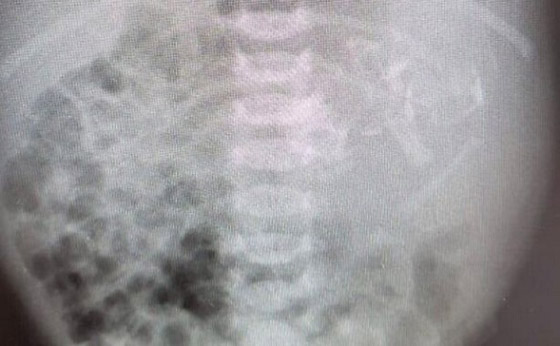

طفلة تولد بحالة نادرة بعد العثور على توأمها داخل معدتها صورة رقم 2

وتشير نظرية أخرى إلى أن FIF هو نوع من الورم المسخي، وهو ورم يمكن أن يحتوي على جميع أنواع الخلايا الثلاثة الرئيسية الموجودة في جنين بشري في مراحله المبكرة. ووفقًا لورقة نشرت عام 2010، يقول الباحثون إن وجود العمود الفقري يميز تشخيص الورم المسخي عن طريق الفم، لأن الأخير لا يحتوي على عمود فقري. ويقول الأطباء إن الطفلة تتعافى بشكل جيد من العملية الخطيرة التي أجريت لإزالة الجنين من بطنها وهي الآن في المنزل مع والدتها.